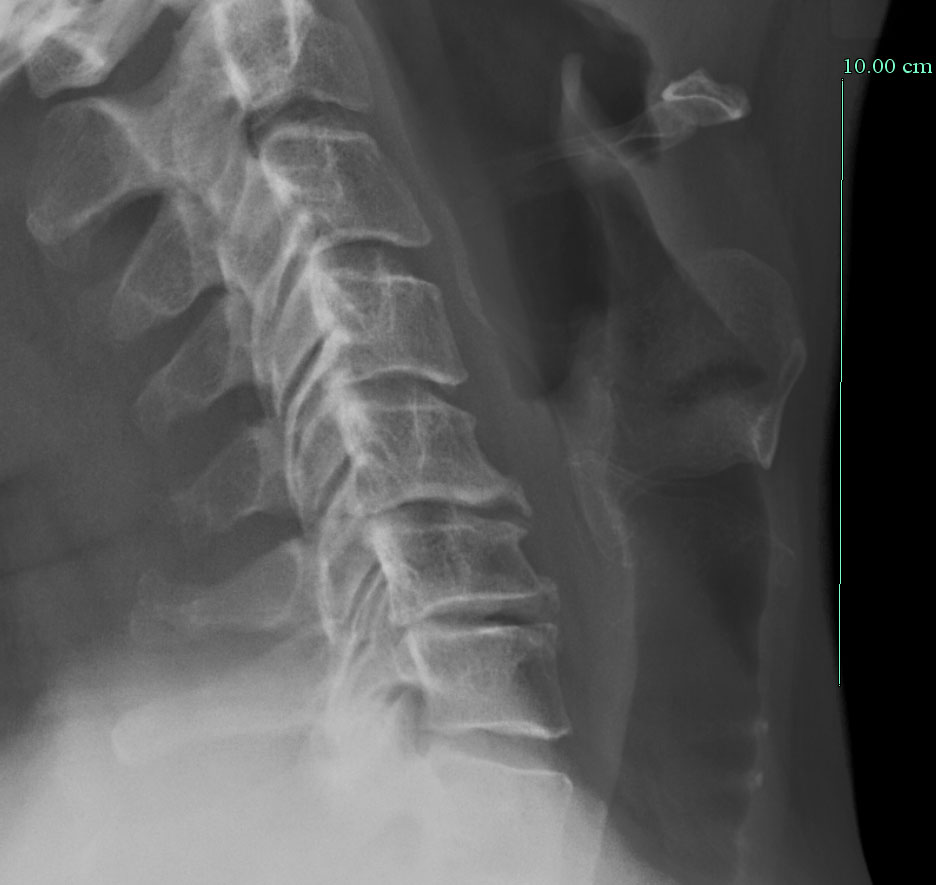

A conventional X-ray taken before surgery. Note the rather sinister "hook" on the front of the affected joints, where the bone is growing over the extruded discs (not visible in this X-ray). This is happening on the back side, which has to be removed. Getting rid of all that crunchy bone without harming the spinal cord is why neurosurgeons get paid a lot.

Contrast this X-ray with the next ones, where you can see the new artificial joints.